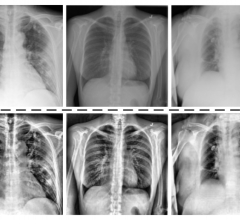

This page contains medical information for clinicians on the 2019 Novel Coronavirus (COVID-19, also called 2019-nCoV and now clinically SARS‐CoV‐2). This section includes articles on medical imaging of the virus for radiologists, new technologies being deployed to fight the virus and clinical information from various sources. Here are direct links for medical professionals to COVID-19 resources from the U.S. Food and Drug Administration (FDA), Centers for Disease Control (CDC) and the World Health Organization (WHO). Daily world-wide statistics on the coronavirus outbreak are available from the WHO Situations Reports. Centers for Medicare and Medicaid Services (CMS) frequently asked questions and answers (FAQs) for healthcare providers regarding Medicare payment for laboratory tests and other services related to the COVID-19

July 10, 2020 — An open-access American Journal of Roentgenology (AJR) article investigating the differences in computed ...

July 9, 2020 — With increased lung CT exam paradigms being used in the current COVID-19 (SARS-CoV-2) outbreak, and an ...